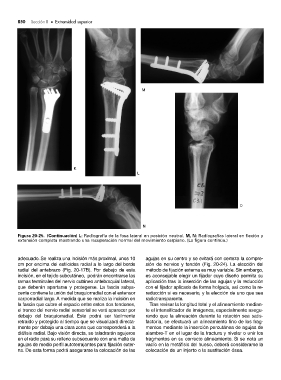

Figura 20-25. (Continuación) L: Radiografía de la fosa lateral en posición neutral. M, N: Radiografías lateral en flexión y

extensión completa mostrando una recuperación normal del movimiento carpiano. (La figura continúa.)